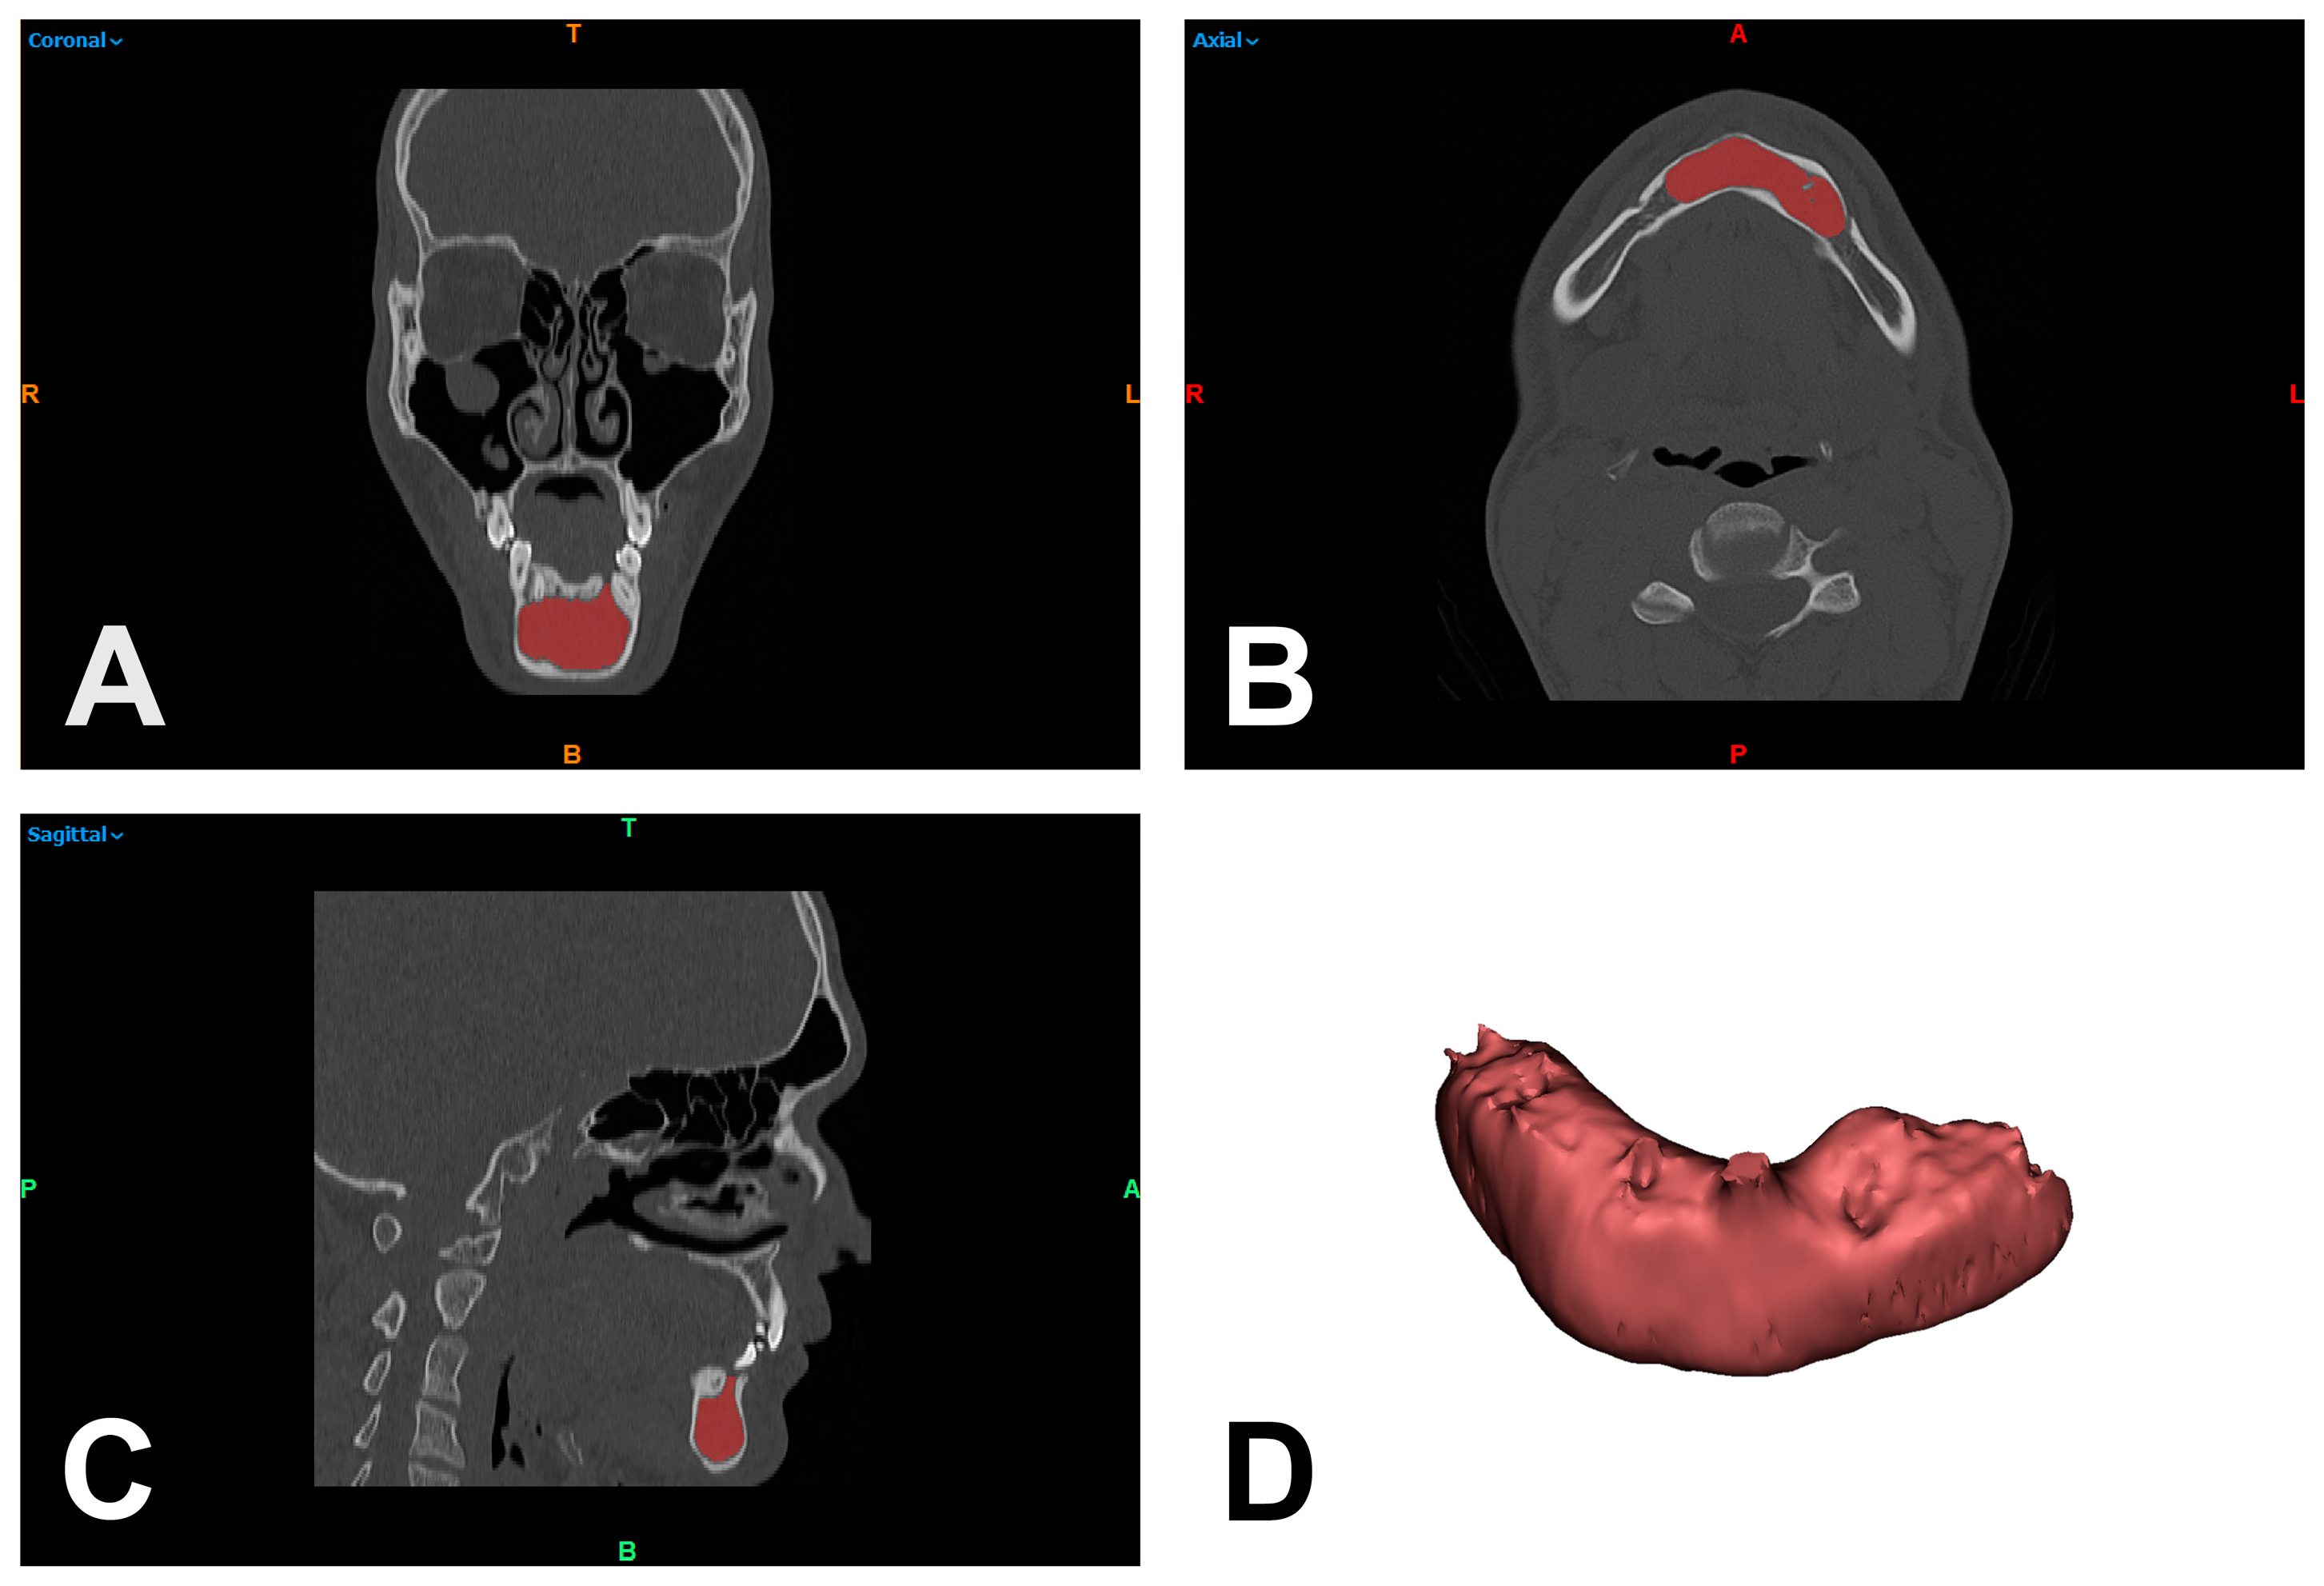

2.2. Hounsfield Unit-Based Quantification of Lesions